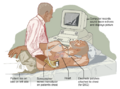

- BasicsOfImagingFig1.svg 475 × 354; 843 KB